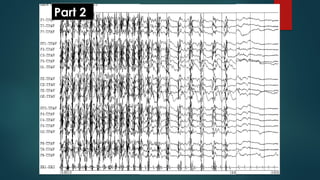

Part 1

Part 2

• #142ย Generalized tonic-clonic seizure (Part 1). Onset of generalized tonic-clonic seizure, longitudinal average ear referential montage. Generalized spike and wave and polyspikes noted at seizure onset (filled arrow), evolving to continuous activation during tonic phase (open arrow). Copyright 2013. Mayo Foundation for Medical Education and Research. All rights reserved. Courtesy of Dr. Jeffrey W. Britton, MD.

• #143ย Generalized tonic-clonic seizure (Part 2). Seizure progresses to clonic phase, showing intermittent bursts of diffuse high frequency activity with progressively longer intervals of suppression between bursts. Post-ictal phase marked by diffuse suppression as noted in the latter portion of the epoch shown. Copyright 2013. Mayo Foundation for Medical Education and Research. All rights reserved. Courtesy of Dr. Jeffrey W. Britton, MD.